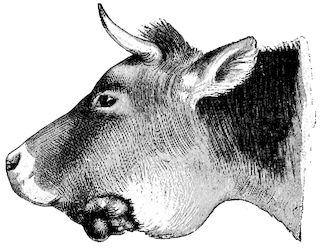

Fig. 4.—Deformity of the face in the horse shown in Fig. 2.

The flat bones are particularly liable to this change, which is common to domesticated animals. The bones of the head are the first to suffer; later those of the pelvis. The lower jaw becomes swollen, particularly about the centre of the branches which may attain three, four, or five times, their normal thickness.

The depression in the submaxillary space disappears. The upper jaw undergoes similar changes, becoming deformed and thickened until the cavities of the sinuses and the hollow appearance of the palate are lost, while the face is so changed that it cannot be recognised as that of a horse, goat, etc.

The molar teeth are almost buried, their tables alone being visible at the bottom of a depression, the edges of which rise above the neighbouring parts (pig).

Mastication is clearly impossible, the jaws appear paralysed, the muscles powerless, and only swallowing is possible, a fact which explains why life is only prolonged to this stage in animals which can be fed with a spoon or bottle (pigs and goats). The bones of the cranium, although greatly changed in texture, are always less deformed than those of the face.

The changes are such that it is often easy with a mere post-mortem knife to cut the head completely in two. Osseous tissue, properly so-called, has disappeared.

All the constituent tissues, with the exception of the skin and muscles, i.e., the bone, periosteum and aponeuroses, have the appearance and consistence on section of the fibro-lardaceous tissue seen in chronic inflammation.

Fig. 5.—Head of a pig suffering from osseous cachexia.

“The disease may advance for two or three months, and in case of pelvic fractures and distortions, there may be permanent lameness, and dangerous obstruction to parturition, even though the bones should acquire their normal hardness through the deposition of lime salts.”

Fig. 7.—Osseous cachexia: softening of the maxillæ.

Fig. 8.—Transverse section through the middle region of the face in a pig suffering from osseous cachexia.

18In the final stages, the bones may be cut with a knife, and a time arrives when bony tissue seems completely to have disappeared; thus, as shown in Fig. 8 herewith, it was possible to cut the entire head of a pig into thin slices without the slightest difficulty. All parts of the head had been affected by the softening change.

From the chemical point of view, the diminution in mineral salts and in phosphate of calcium has long been recognised, but the degree of this change varies according to the phase. In human beings the proportions have been estimated as follows: Normal bone, 50 to 80 per cent. of phosphate of calcium; bone in persons suffering from osteomalacia, 5 to 20 per cent. of phosphate of calcium. The changes in the ossein have not been carefully studied. We only know that histologically the ossein becomes fibrillar, and that chemically it no longer retains its normal composition.